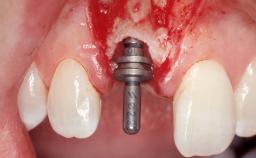

Immediate Flapless Placement of an Implant in a Maxillary Left Central Incisor Site

A 29-year-old female patient presented for treatment to replace the upper left central incisor tooth with an implant- supported restoration. The tooth had been intermittently symptomatic for the previous 12 months. The tooth had originally suffered trauma about 15 years previously. Several endodontic treatments had been performed, including an apicectomy procedure to retain the tooth. The patient was healthy and a non-smoker. She had reasonable expectations in regard to esthetic outcomes and the risk of marginal tissue recession following treatment. At medium smile, the gingival margins of the upper teeth were visible, with a display of 3 to 4 mm of the gingival margins. Gingival recession of tooth 21 and a discrepancy in the gingival levels between teeth 11 and 21 was observable during normal speech and smile.

| Placement Protocol | Immediate implant placement |

| Tooth Site | Maxillary incisor or canine |

| Socket Morphology | Single-root socket |

| Socket Integrity | Damage to one or more bone walls |

| Bone Volume | Damage to one or more socket walls |